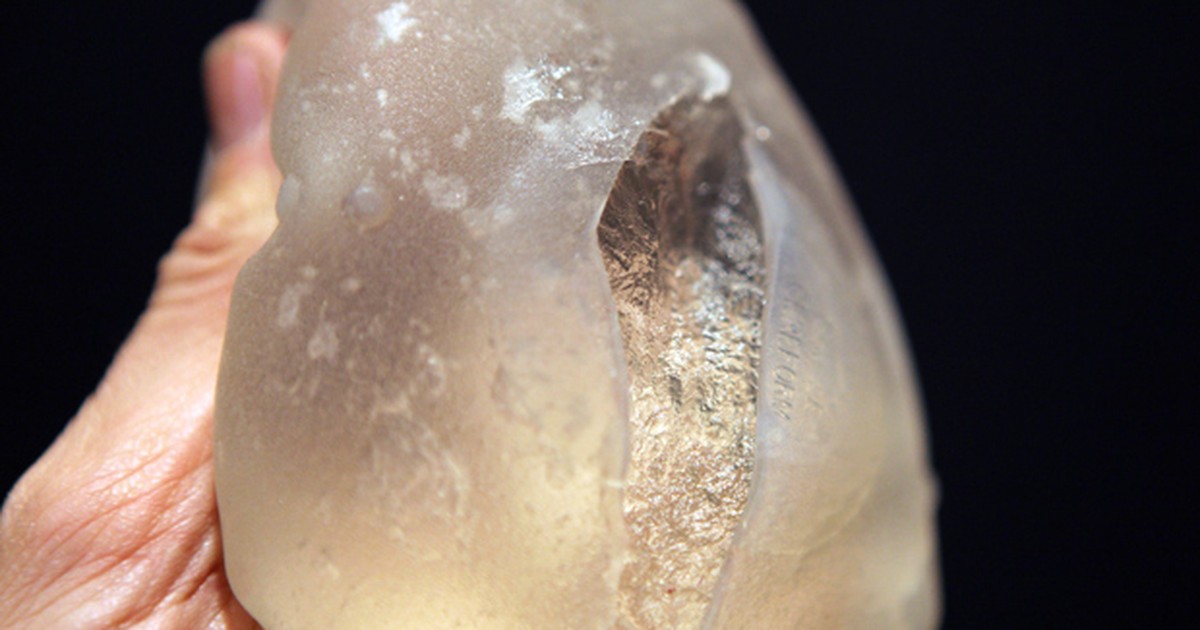

Breast implant ruptured